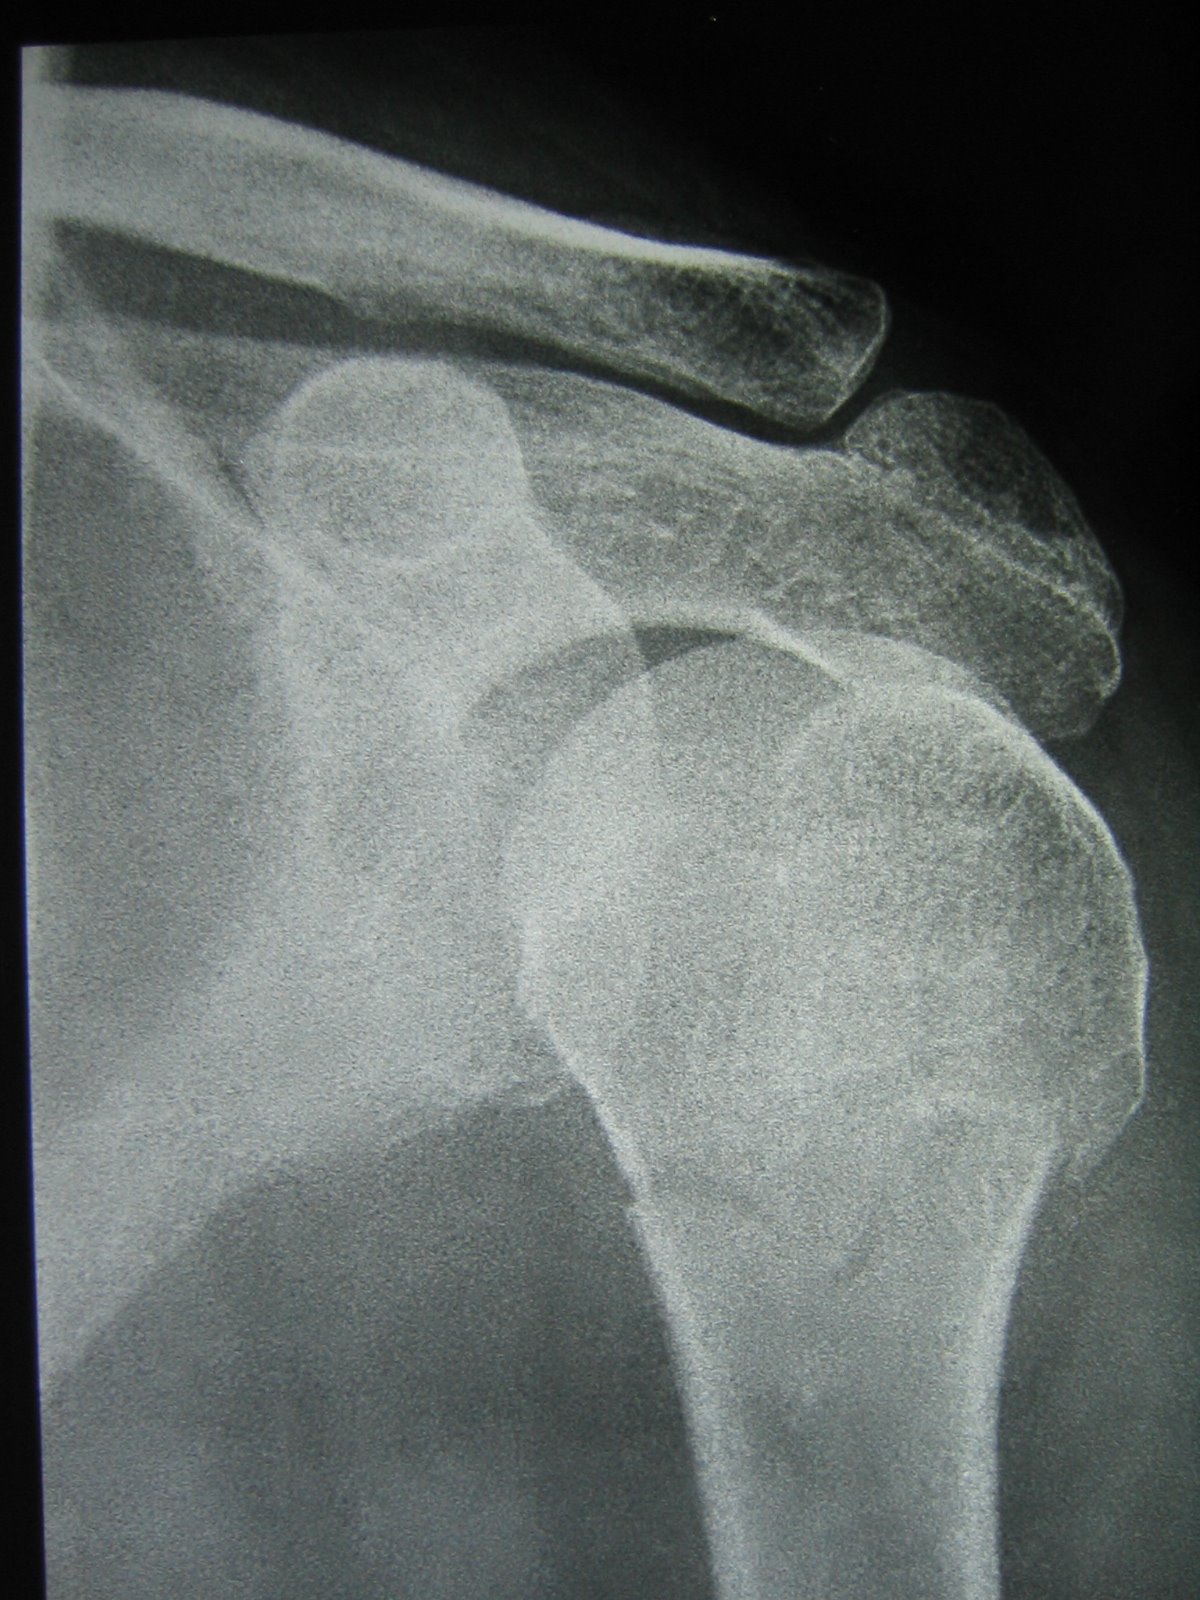

Shoulder Fracture X Ray . The neer classification of proximal humeral fractures is probably the most frequently used system along with the ao classification of proximal humeral fractures. The shoulder joint is between part of the scapula or shoulder blade (blue line) and the proximal humerus (green line). Soft tissue areas, cortical margins, trabecular patterns,bony alignment, joint. However, a doctor may request additional imaging, such as a ct. A recommended systematic checklist for reviewing musculoskeletal exams is: Magnetic resonance imaging (mri) :

Xray.Shoulder.Fracture (image)